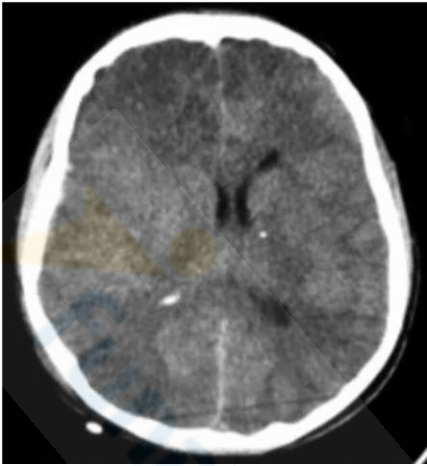

No traumatismo cranioencefálico, a correta identificação das lesões estruturais é de suma importância para determinar o tratamento a ser empregado. Considerando esse fator, analise a Figura 2 abaixo:

Figura 2

Considerando um desvio da linha média de 6 mm e sem lesões >25 mL, assinale a alternativa correta sobre a classificação de Marshall apresentada no exame e sua definição.